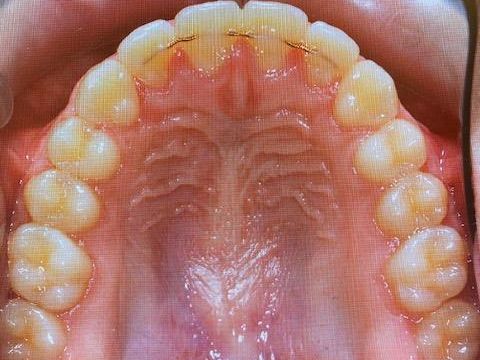

Quad Helix regulering på tenner i overkjeve

Annen apparatur

Ved behov benyttes også annen reguleringsapparatur, blant annet Quad Helix og tommelfingersperre. Valg av apparatur tilpasses bitt og tannstilling.